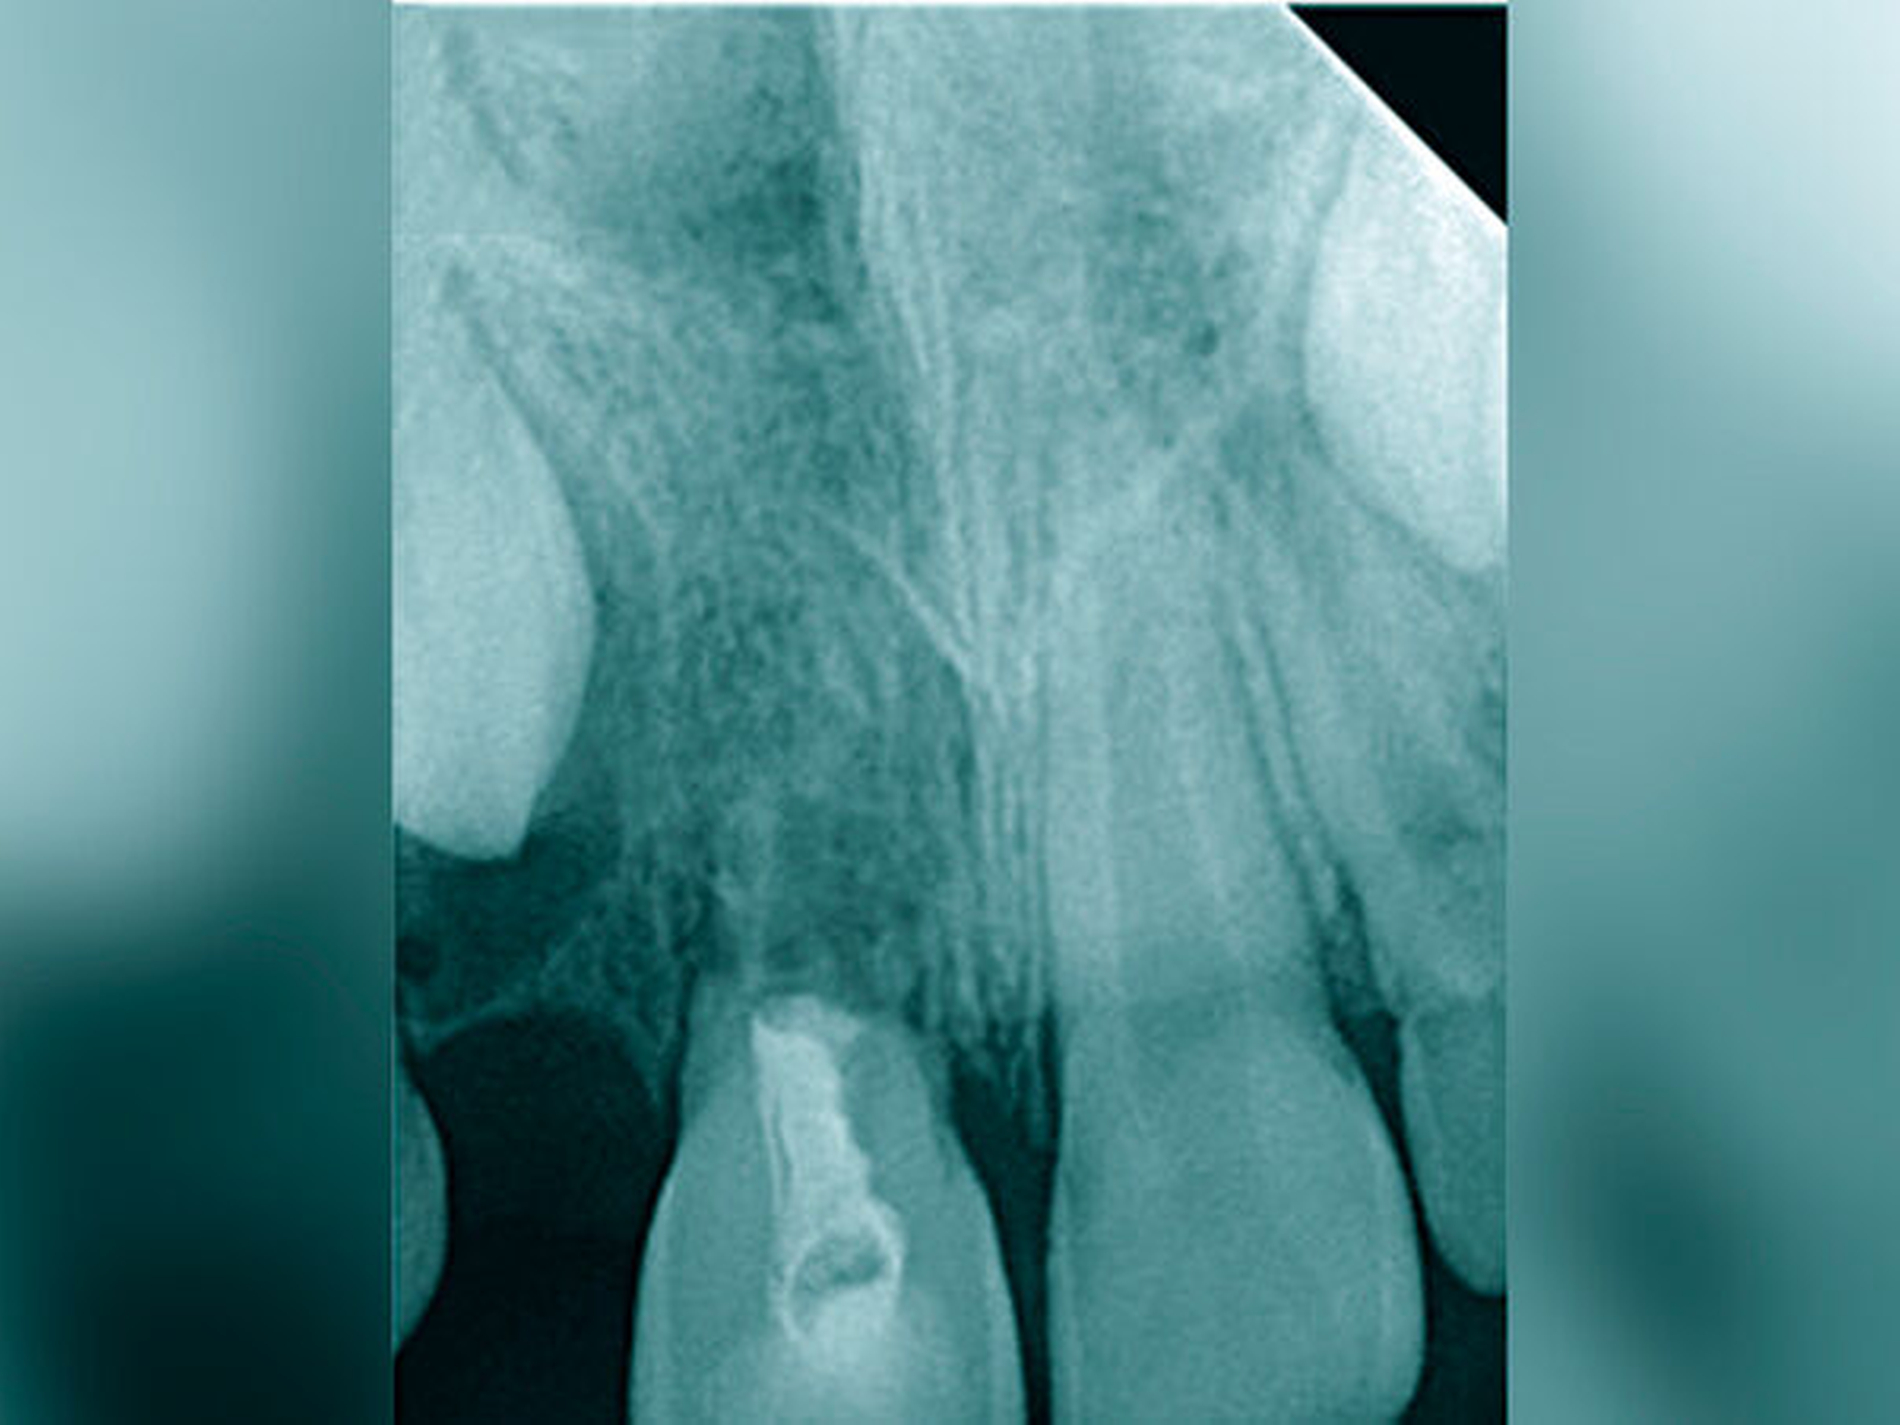

Die Häufigkeit für den Frontzahnverlust beträgt drei bis vier Prozent. Die Altersgipfel liegen zwischen dem achten und dem neunten sowie vom zwölften bis zum 14. Lebensjahr. Betroffene Zähne sind der mittlere und der seitliche Schneidezahn im Oberkiefer. Es besteht eine Korrelation der Häufigkeit zu den Zahnstellungsanomalien der vergrößerten sagittalen Schneidekantenstufe, dem schmalen Deckbiss mit protrudierten seitlichen Schneidezähnen und progen stehenden Einzelzähnen. Obwohl bei Avulsion die sofortige Reimplantation zum Erhalt des Zahnes führen kann, sind häufig Ankylosen des Parodonts und Wurzelresorptionen mit begrenzter Erhaltungswürdigkeit die Folgen. Eine fehlende Sensibilität, ein hoher Klopfschall und der röntgenologische Resorptionsnachweis sind diagnostische Anzeichen dafür.

Erfolglose Reimplantation (Wurzelresorption und Lockerung)

Fehlender Abschluss des Wurzelwachstums, weites Foramen apikale und Avitalität. Eine endodontische Aufbereitung ist aufgrund des divergierenden Wurzelkanals schwierig.

Das Wurzelwachstum des Transplantats sollte zum Zeitpunkt der Entnahme nicht mehr als zwei Drittel betragen. Dies kann eine operative Freilegung notwendig machen (Abb. 3).